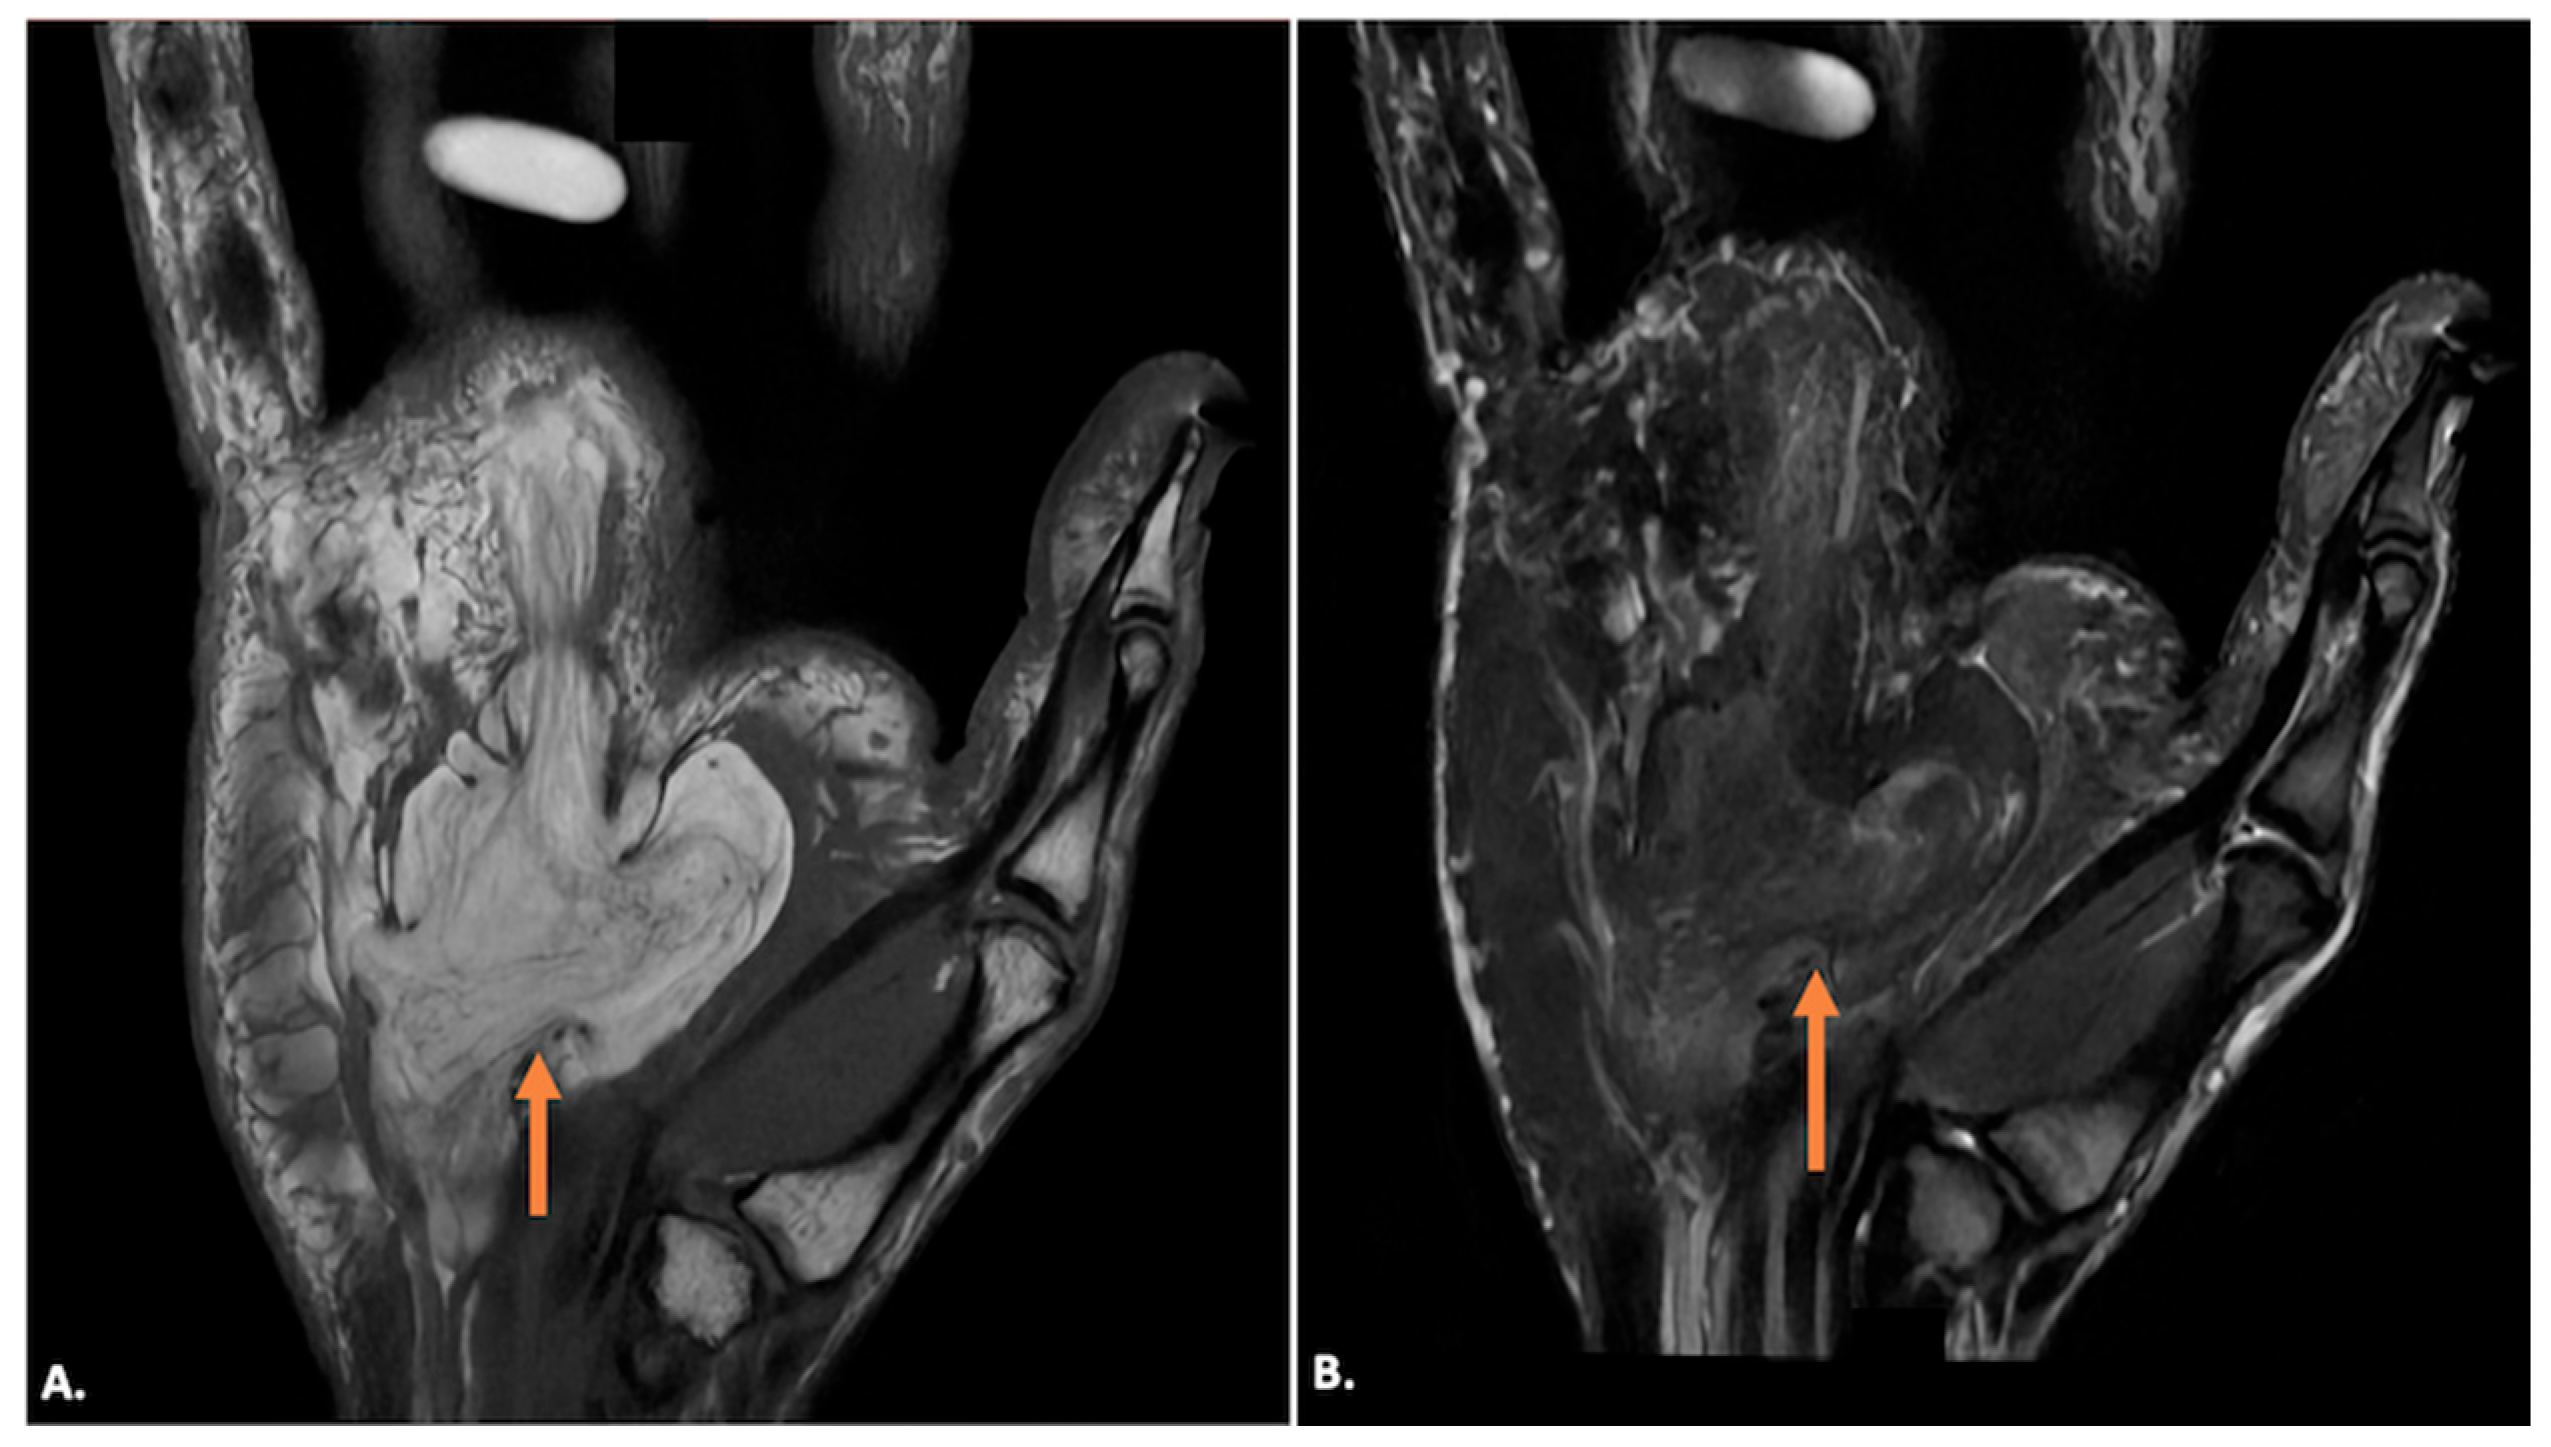

Lipomas appear as a well-defined, homogeneously iso-to-hypoechoic mass on ultrasound imaging corresponding to fat, and there is usually no internal vascularity on Doppler. It may have echogenic striations within the lesion. On MRI, lipomas are typically hyperintense on both T1- and T2-weighted images due to their high-fat content and demonstrate homogeneous fat suppression on fat-suppressed sequences (Figure 9). No internal enhancement is seen after gadolinium contrast administration. The presence of septa and nodules may point towards atypical lipomatous lesions (Figure 10) [18]. Hemangiomas present as hypoechoic or heterogeneous masses on ultrasound imaging, often containing anechoic areas corresponding to vascular channels. Doppler imaging will demonstrate significant internal vascularity with low-resistance arterial and venous flow patterns. On MRI, haemangiomas are hyperintense on T2-weighted images due to the high fluid content and show low signal intensity on T1-weighted images. Following contrast administration, they exhibit intense, heterogeneous enhancement.

Figure 9.

(A) T1-weighted coronal, (B) T1-weighted, fat-saturated coronal, and (C) T1-weighted axial and (D) T1-weighted fat-saturated axial MR images showing a typical lipoma (arrow) in Guyon’s canal, appearing as a T1-weighted hyperintense lesion (A,C) filling the Guyon’s canal with complete suppression of fat signals on T1-weighted, fat-saturated sequences (B,D).

Figure 10.

(A) T1-weighted coronal and (B) post-contrast T1-weighted, fat-suppressed coronal MR images showing an atypical lipomatous lesion (indicated by orange arrows) in Guyon’s canal, showing T1-weighted hyperintense lesion with hypointense septa in (A) with complete suppression of fat signals and enhancement of the septa in (B).